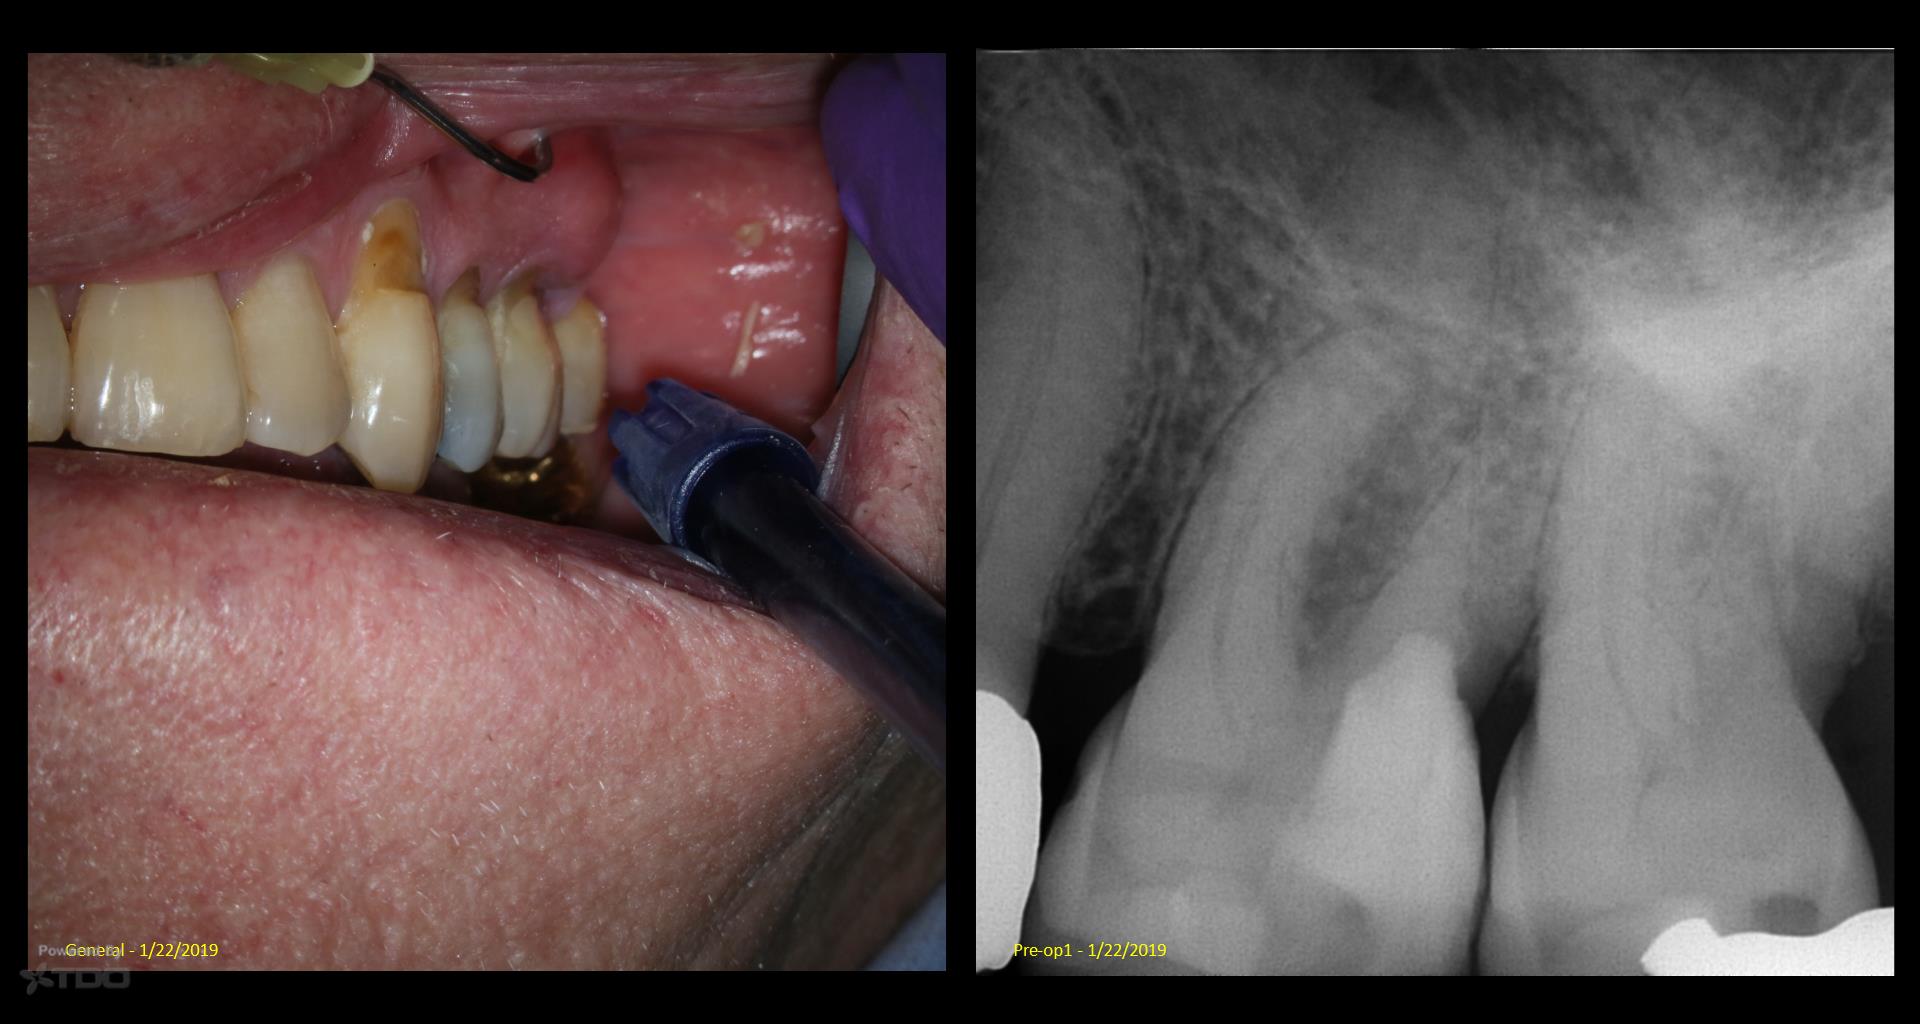

Fascinating read about the 1 year GW recall. The visual aid teeth cleaning image by doctor elevates the comprehension of the subject matter and makes the content more engaging. Fence Decking Supplier in Toms River NJ

Fascinating read about the 1 year GW recall. The visual aid teeth cleaning image by doctor elevates the comprehension of the subject matter and makes the content more engaging.